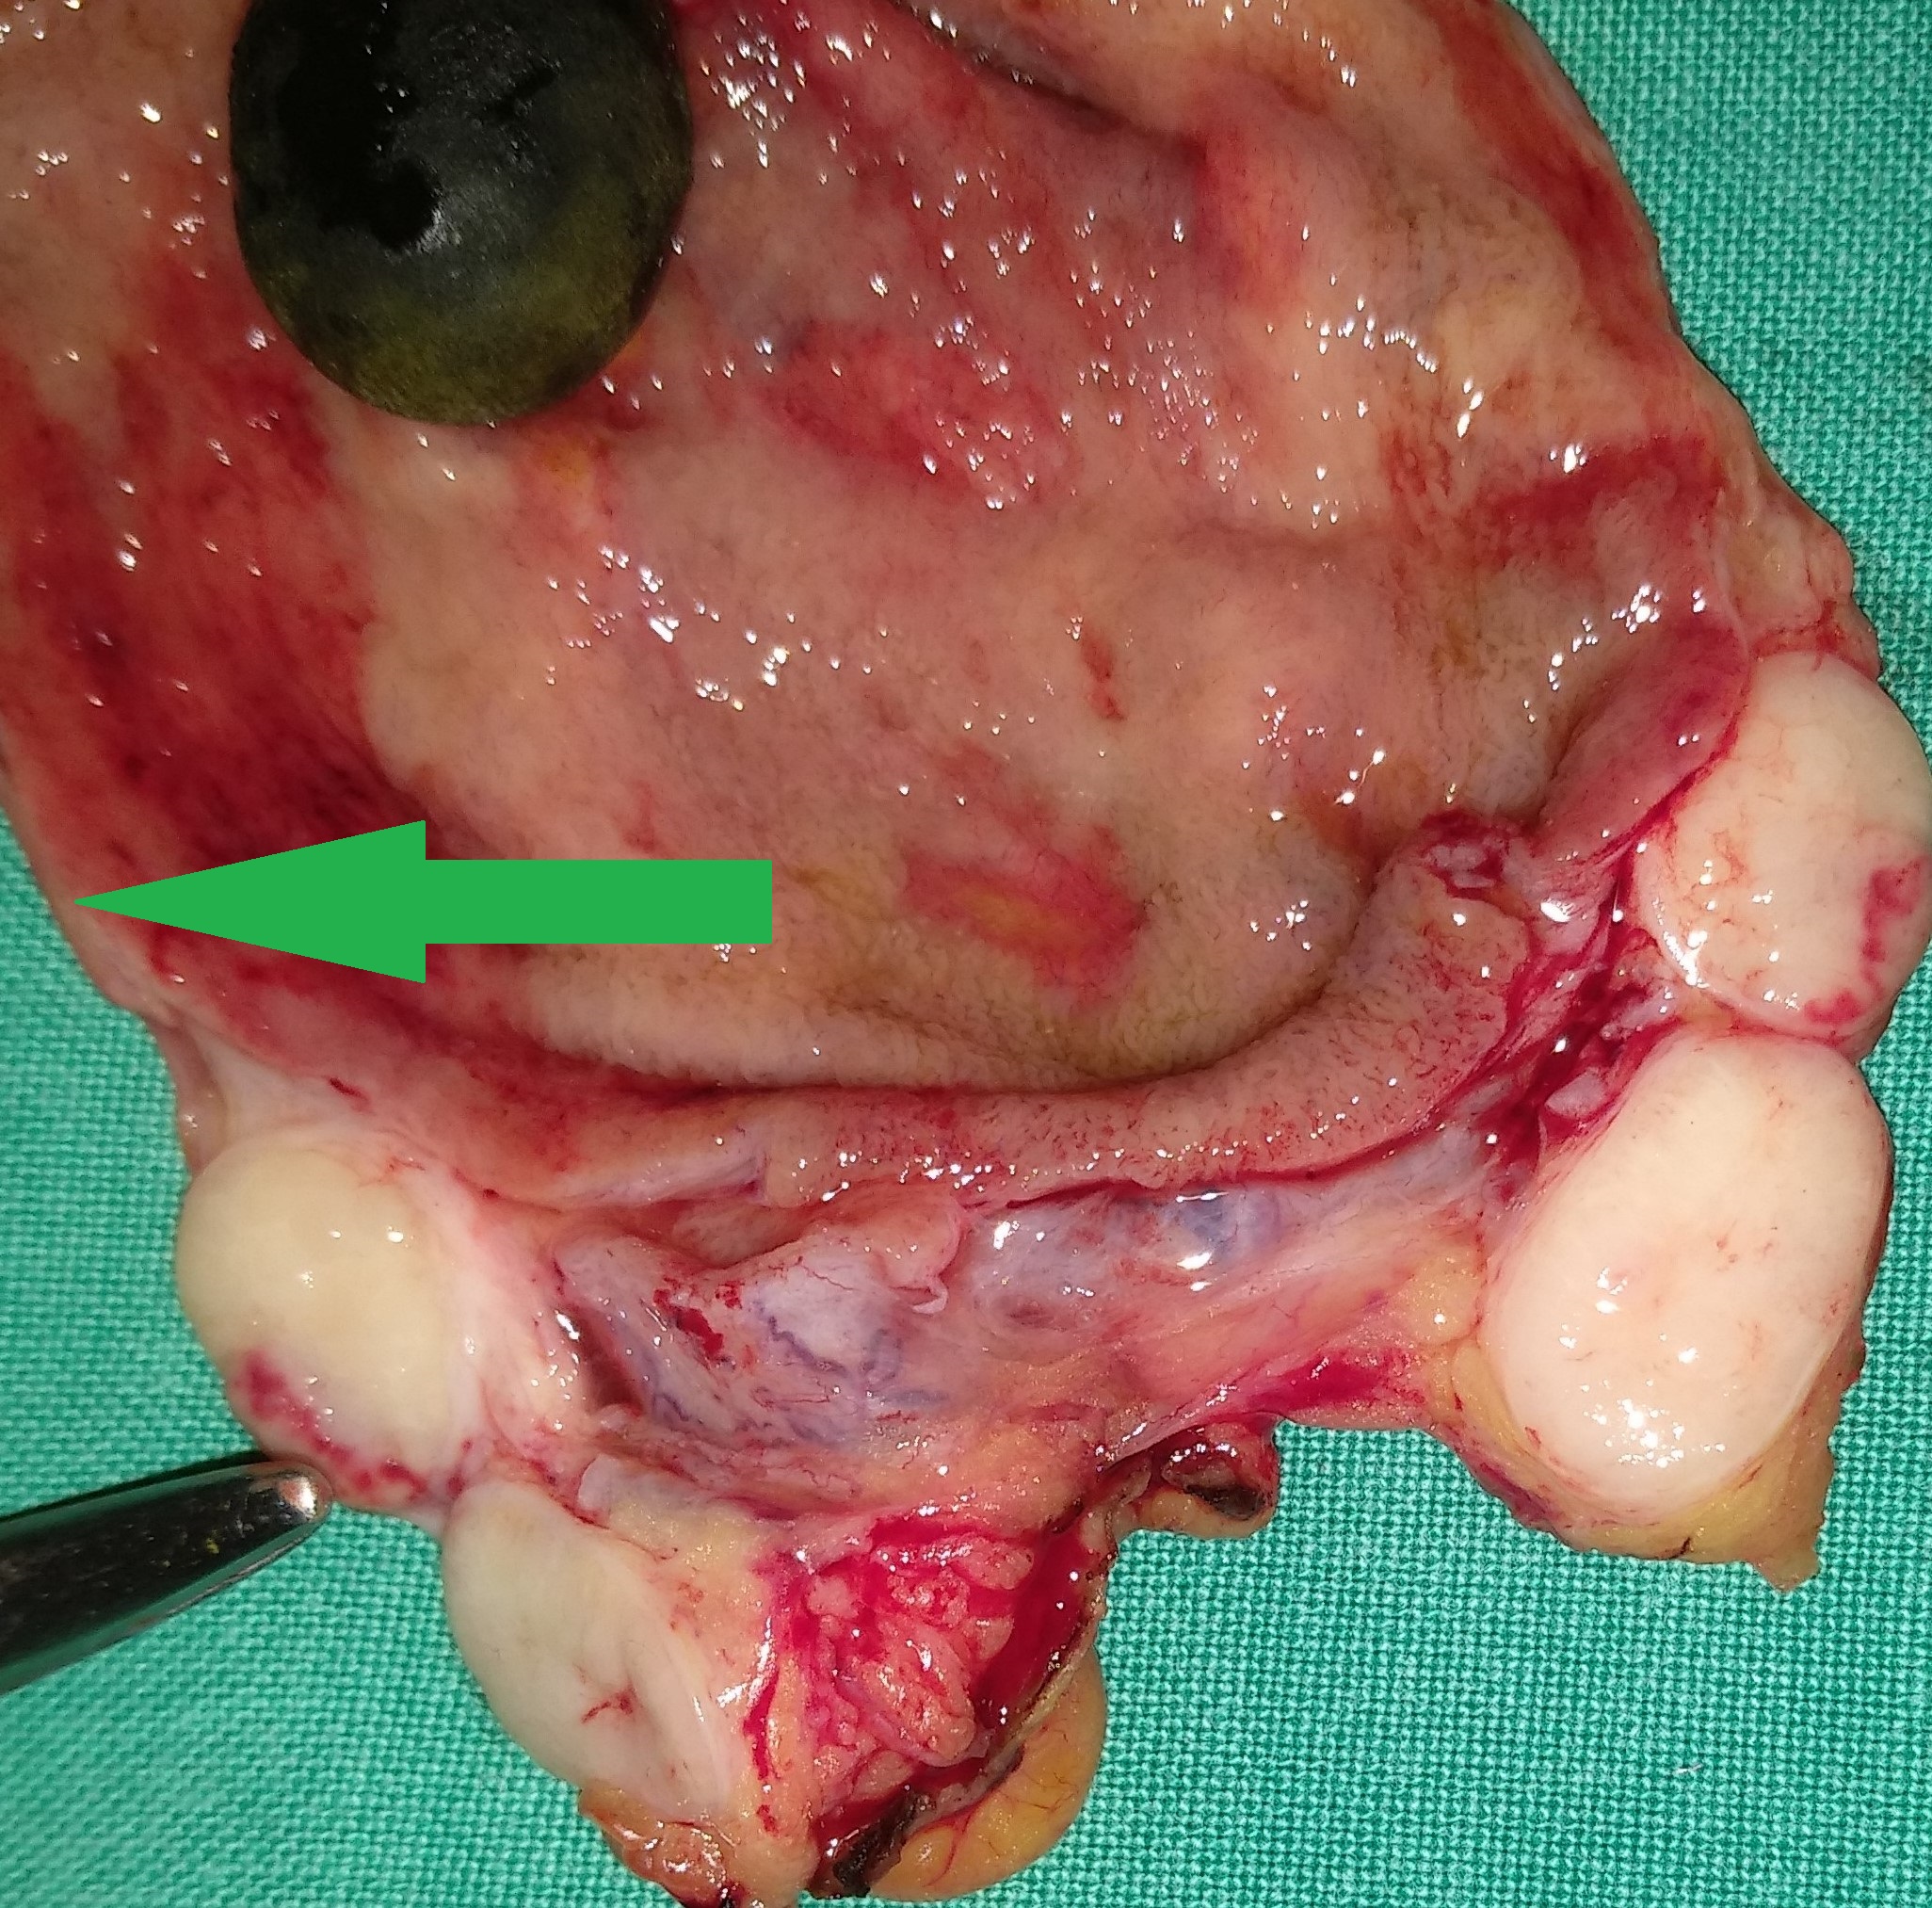

Liver after resection of the infected cyst. Presence of hemostatic Surgicel on the raw surface (Courtesy Dr. V. Penopoulos)